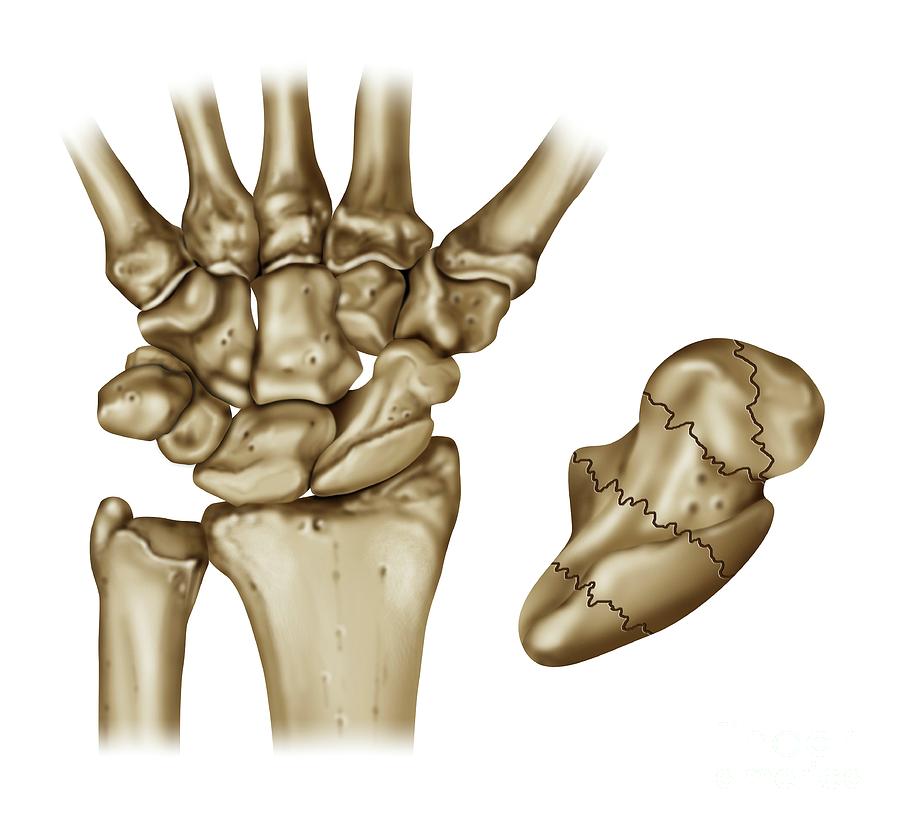

Scaphoid (Navicular) Fractures – Dr. Groh

Scaphoid fracture causes, symptoms, diagnosis, treatment & revovery time

A Rare Isolated Trapezoid Fracture – The Western Journal of Emergency …

Scaphoid Fracture Of The Wrist Photograph by Maurizio De Angelis …

Scaphoid Fracture of the Wrist | eOrthopod.com